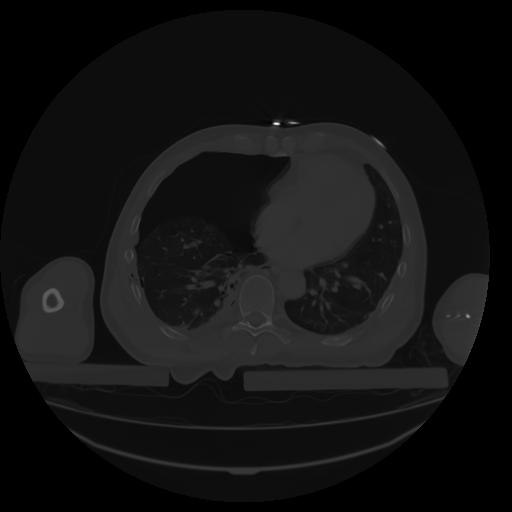

27 CUERPO,CE,Axial,3.0,CUERPO,,